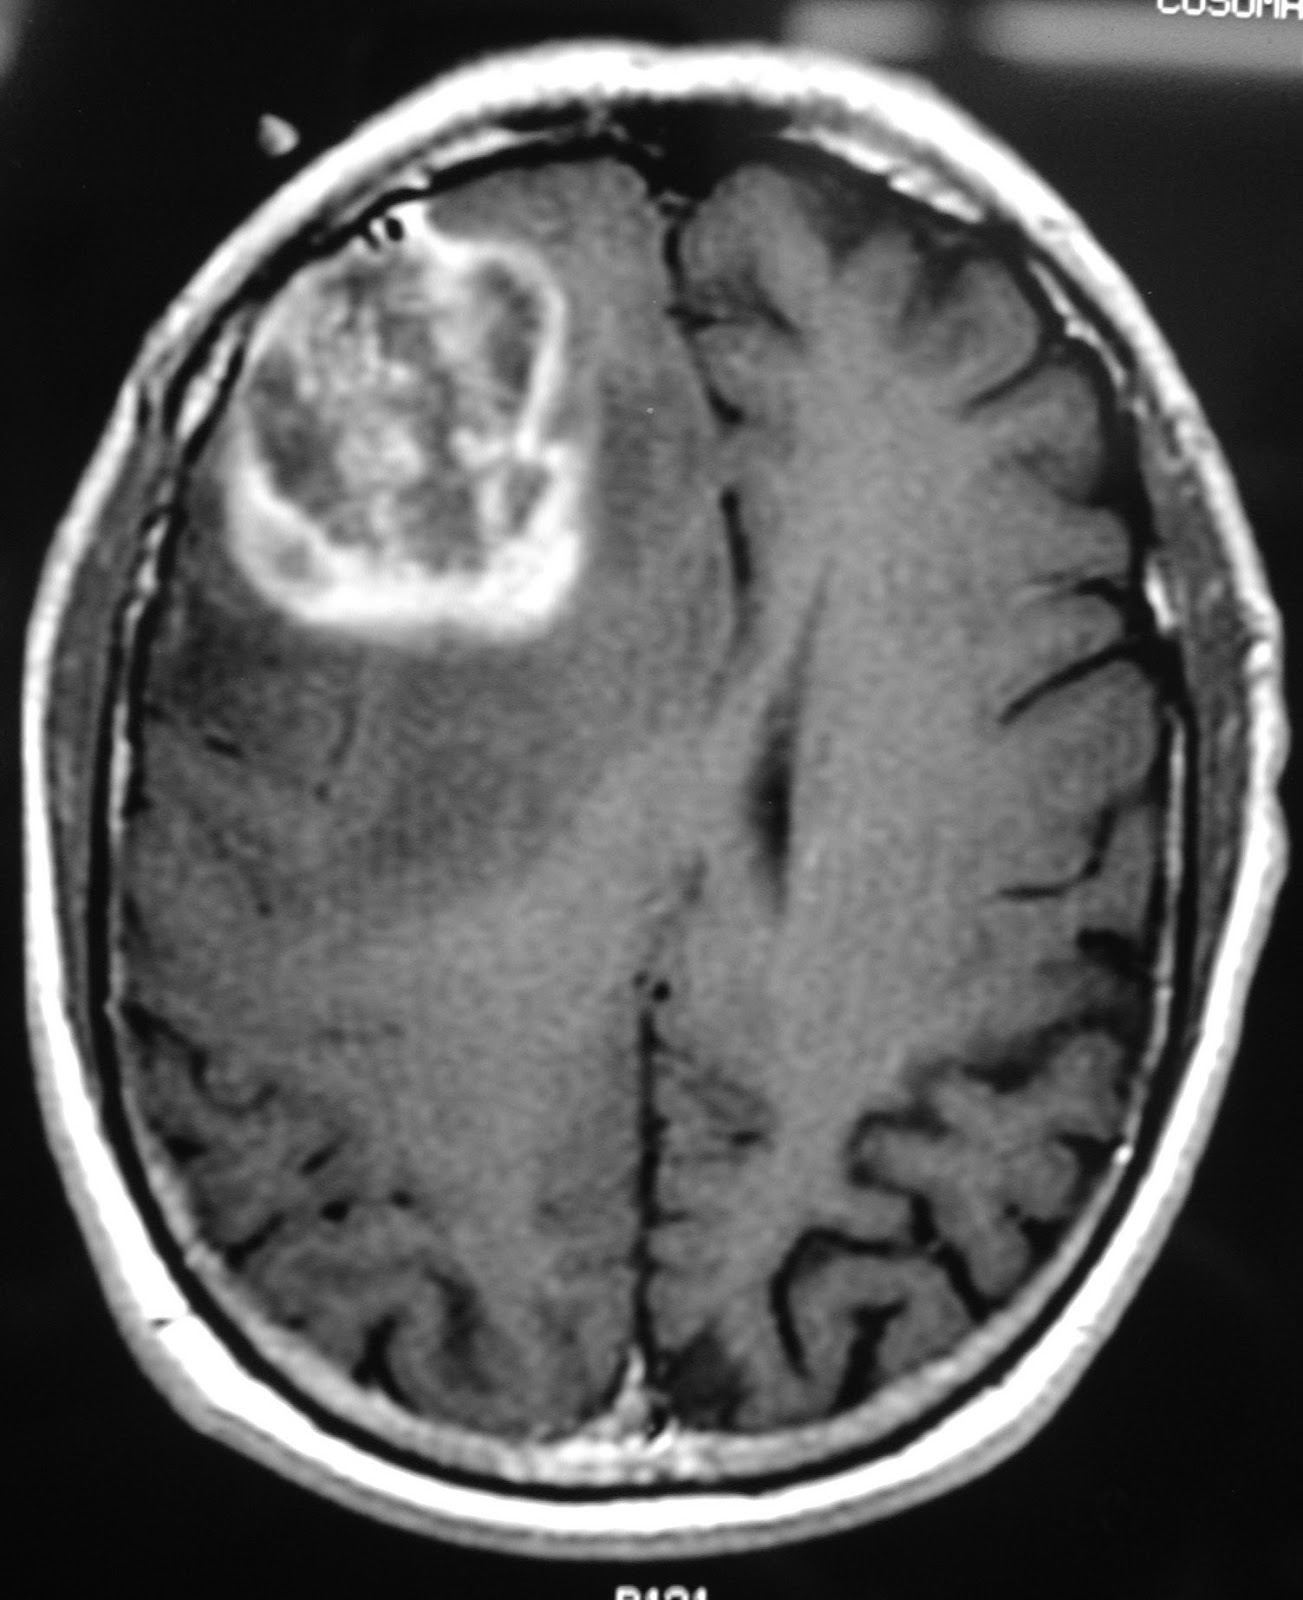

En este caso hablamos de un glioblastoma, es un tipo de glioma, un tumor que nace de las células de soporte del tejido cerebral. En el paciente, el cáncer se había propagado.

El proceso consistió en retirar con cirugía la mayor parte del tumor y después introducir las células modificadas que consiguieron parar el desarrollo de el glioblastoma.

Pero el cáncer volvió y otra vez se aplicó el tratamiento pero con un pequeño cambio, las células fueron directamente inyectadas en los ventrículos del cerebro, lo cual es muy arriesgado pero dió resultados. El tumor no solo se redujo sino que también se ha remitido, esto ocurrió en solo un año.